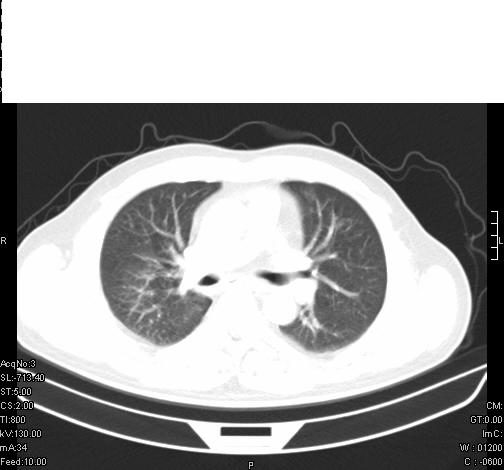

标题: CT6685:右肺阻塞性炎症,增强CT。 [打印本页]

标题: CT6685:右肺阻塞性炎症,增强CT。

前几天,发了患者的平扫片,患者抗炎一周后增强扫描。右中叶病灶吸收明显,但下叶病灶未见明显吸收。右肺门可见结节影,看来凶多吉少

右肺下叶支气管管腔狭窄,管壁增厚,右下肺见斑片状高密度影,考虑右侧肺门中心肺癌伴阻塞性肺炎

右肺下叶散在的斑片状致密影,下叶支气管变窄。考虑:右肺慢性炎症。

第18幅,好像不能简单用炎症解释,前几天我发平扫时,90%人支持肺癌,现在好像大家更倾向于炎症了,我觉得还是不能排除肺癌。

右肺下叶支气管壁明显增厚,考虑癌症并阻塞性炎症、肺门淋巴结肿大

考虑右肺癌并阻塞性炎症、肺门淋巴结肿大

右肺下叶支气管壁不规则增厚,右肺下叶有斑片状影分布。考虑右肺中央型肺癌伴右肺下叶阻塞性改变。建议支纤镜检查。平扫比增强较好显示了病变情况。

右主支气管狭窄,管壁增厚。考虑右中心性肺ca伴阻塞性肺炎。

既然抗炎治疗有效,可继续治疗;右肺下叶支气管管腔狭窄,管壁增厚,右下肺见斑片状高密度影,右侧主支气管后见结节影(淋巴结?),肺癌不能排出。